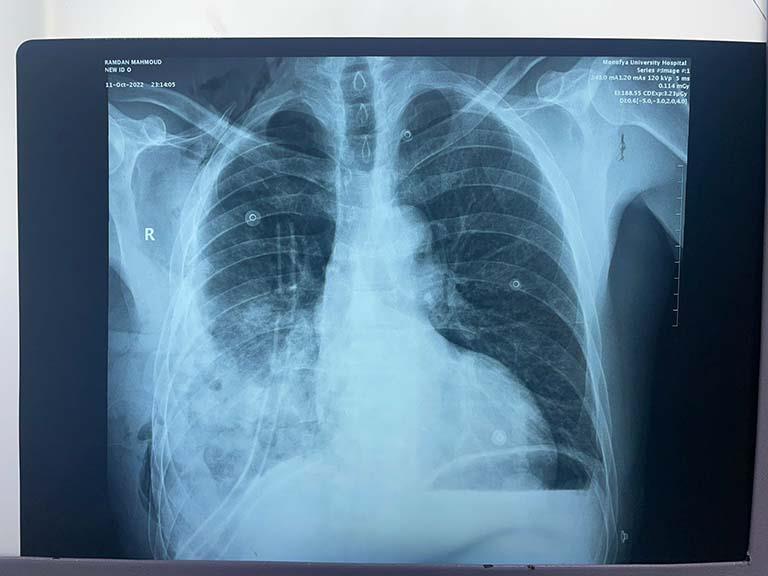

نجح فريق من أطباء جراحة القلب والصدر بمستشفيات جامعة المنوفية، اليوم الخميس، برئاسة الدكتور محمد الحاج علي الأستاذ المساعد بالقسم، في استئصال ورم بالصدر لحالة مرضية أبعاده 17 سم x 19 سم، ويزن تقريبا 4 كيلو جرام.

وأشار الدكتور محمد الحاج علي رئيس الفريق الجراحي بأن المريض يبلغ من العمر 58 عامًا يعاني من ضيق بالتنفس، وبعد عمل الفحوصات الطبية المختلفة من أطباء علاج الأورام بالمستشفيات تبين وجود ورم بتجويف الصدر ووضعت خطة علاج و خضوع المريض للعلاج الكيماوي لمدة 4 أشهر.

جرى أخذ عينة من الصدر وأظهرت عدم استجابة الورم للعلاج الكيماوي، واتخاذ القرار بدخول المريض عمليات جراحة الصدر وعمل استكشاف صدري لاستئصال الورم، وخضع المريض للمتابعة بقسم جراحة القلب والصدر بالمستشفيات الجامعية.